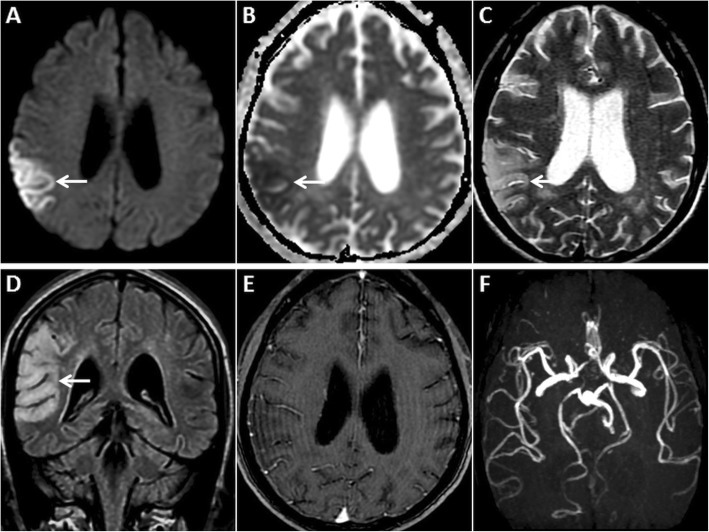

MRI of the brain performed in the subacute phase of HIE. DWI hyperintensity is noted in the deep grey nuclei and extensively in the cerebral cortices (arrows) on axial DWI image (a). There is no signal drop on axial ADC image (b). Diffuse cortical swelling and signal changes (arrows) are appreciated better on the axial T2W image (c). Minimal intraventricular blood (dashed arrow) is seen on axial GRE image (d). Axial source 3D-TOF MRA image (e) and reconstructed maximum intensity projection MRA image of Circle of Willis (f) show no flow signal in the intracranial arteries

Haemodynamic alterations: post-ictal changes